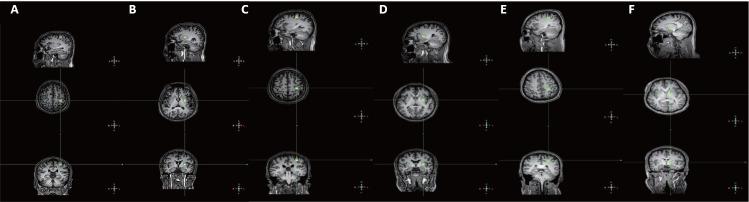

Spinal cord injury is a severe and devastating disease, and spasticity is a common and severe complication that is notoriously refractory to treatment. However, the pathophysiological mechanisms underlying spasticity and its development remain largely unknown. The goal of the present study was to find differences, if any, in metabolites of the left precentral gyrus and basal ganglia of patients who have spinal cord injury with or without spasticity, and to explore the relationship between the brain metabolite concentrations and clinical status. Thirty-six participants were recruited for magnetic resonance spectroscopic examination: 23 with spinal cord injury (12 with spasticity and 11 without spasticity) and 13 healthy controls. We acquired localized proton spectra from the precentral gyrus and basal ganglia via 10 mm voxels. Notably, univariate linear regression analysis demonstrated that the lower that the N-acetylaspartate concentration (a marker for neuronal loss) was in the precentral gyrus of the patients, the lower their ASIA (American Spinal Injury Association) light-touch scores, pinprick scores, and motor scores. Additionally, longer durations of injury were associated with higher N-acetylaspartate levels in the precentral gyrus. Compared with the healthy participants and patients without spasticity, N-acetylaspartate levels in the patients with spasticity were significantly lower in both the precentral gyrus and basal ganglia. Lower N-acetylaspartate levels also correlated with greater sensory and motor dysfunction in the patients who had spinal cord injury with spasticity.

脊髓损伤是一种严重且具有破坏性的疾病,痉挛是一种常见且严重的并发症,其治疗 notoriously 难治。然而,痉挛及其发展背后的病理生理机制在很大程度上仍不清楚。本研究的目的是找出脊髓损伤伴或不伴痉挛患者左中央前回和基底神经节代谢物的差异(若有),并探讨脑代谢物浓度与临床状况之间的关系。招募了36名参与者进行磁共振波谱检查:23名脊髓损伤患者(12名有痉挛,11名无痉挛)和13名健康对照者。我们通过10毫米体素从前中央回和基底神经节获取局部质子谱。值得注意的是,单变量线性回归分析表明,患者中央前回中N - 乙酰天门冬氨酸浓度(神经元丢失的标志物)越低,其美国脊髓损伤协会(ASIA)轻触觉评分、针刺评分和运动评分就越低。此外,损伤持续时间越长,中央前回中N - 乙酰天门冬氨酸水平越高。与健康参与者和无痉挛患者相比,有痉挛患者的中央前回和基底神经节中N - 乙酰天门冬氨酸水平均显著降低。较低的N - 乙酰天门冬氨酸水平也与脊髓损伤伴痉挛患者更严重的感觉和运动功能障碍相关。